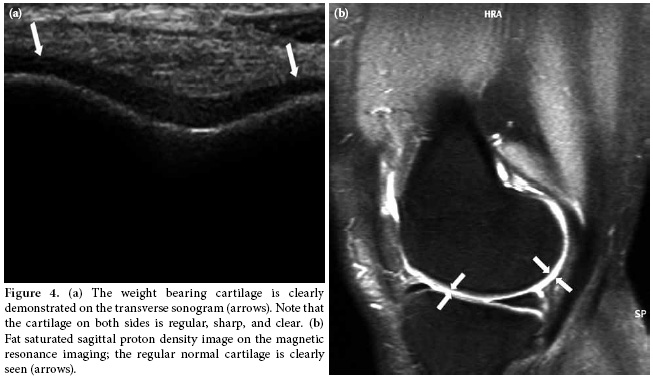

In the second position, the weight bearing medial and lateral femoral condylar cartilage thickness and clarity were evaluated with the knee in maximum flexion. The femoral condylar cartilage was measured on the weight-bearing area approximately 1.5 cm away from the intercondylar notch (Figure 3). The cartilage morphology was assessed using a scale: 1 for regular-clear (Figure 4a, b) and 0 for irregular, non-clear (Figure 5a, b). Finally, all the patients were evaluated for popliteal cysts with the knee extended in a prone position, and any presence of popliteal cysts was recorded.

It is known that a normal femoral condylar cartilage has a clear, smooth and homogeneous hypoechoic appearance parallel to that of the cortical bone on US. Ultrasound has great potential to identify the normal cartilage and allows for differentiation of the abnormal morphology such as loss of clarity, irregularity, and defects on the surface.[7,19] We believe that in the present study, the high concordance rates with MRI have confirmed the accuracy of US in the assessment of cartilage morphology contrary to cartilage measurements.